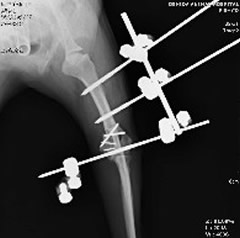

創外固定手術

数種類のピンで小さな骨を安定させた後、皮膚の外から固定する方法を実施しています。

創外固定外観

外観は痛々しいですが、早期に歩行が可能となりました。